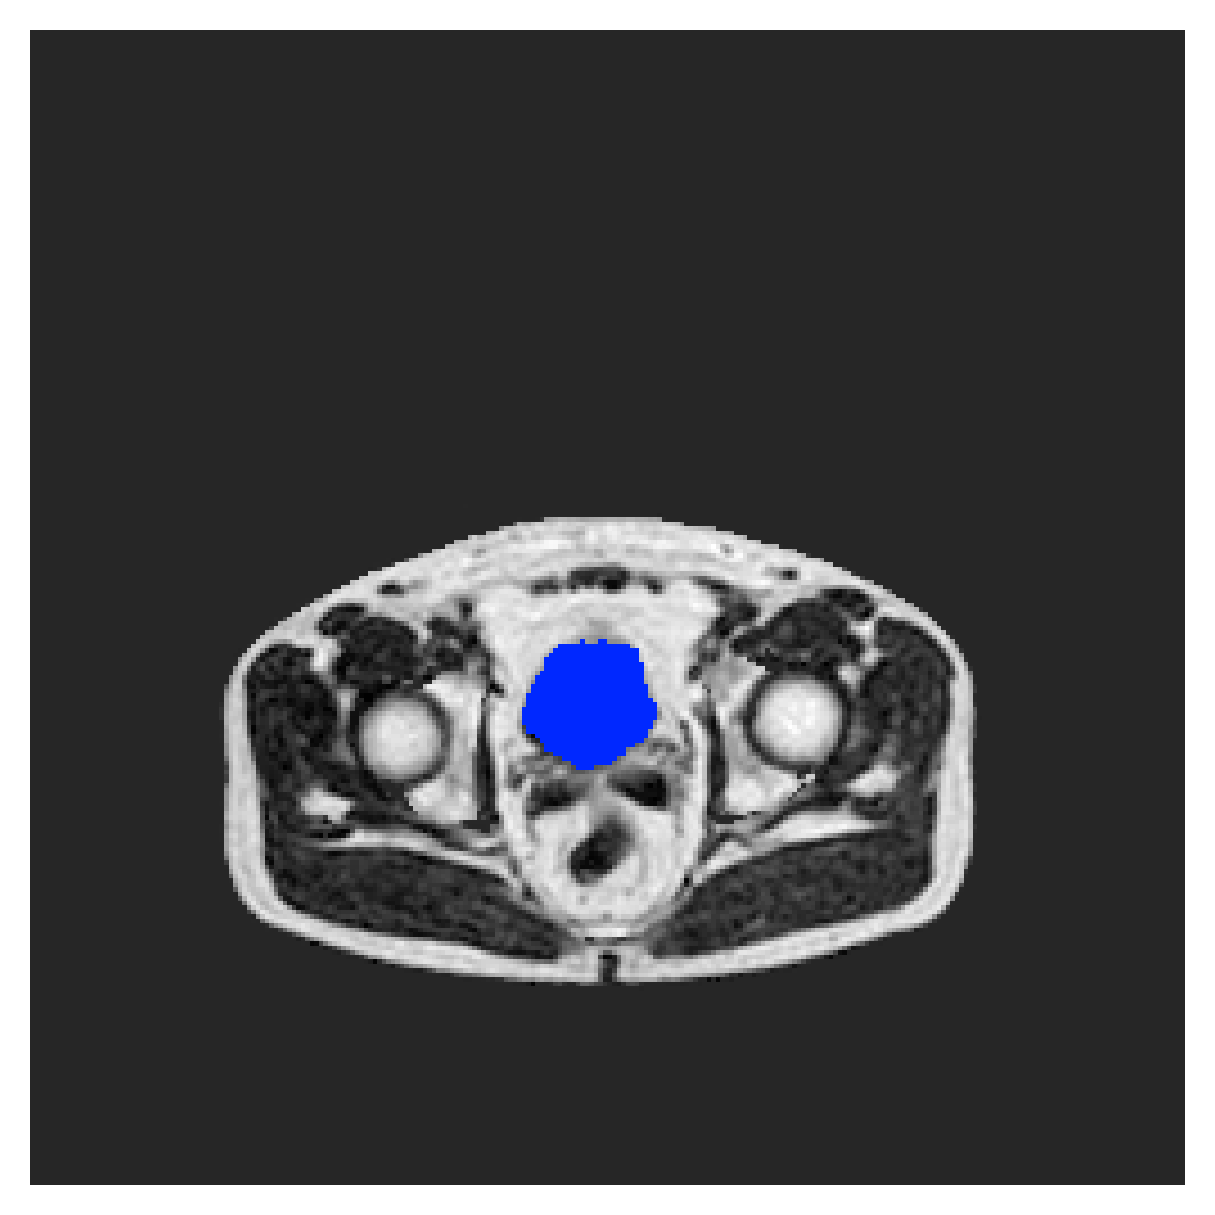

We normalize the volumes and resize the slices to pixels. As the official dataset comes with full annotations, we create a synthetic point ground truth. This is done by first randomly choosing the centers of the point annotations within the class masks, followed by filling an ellipse with axes lengths of and (in pixels) around each center. The intersections of these elliptic discs with the underlying full annotations are then used as our point ground truth. See Figure 2 for an example of the created weak annotation mask. The point annotations are created for every slice, one for each foreground object present in the slice.

The images contain two channels, one for water and one for fat content. For training, we normalize the volumes (per channel) and use 2D slices in the coronal plane, sized . The weak annotations are created synthetically, following the same procedure as described for the ACDC dataset.